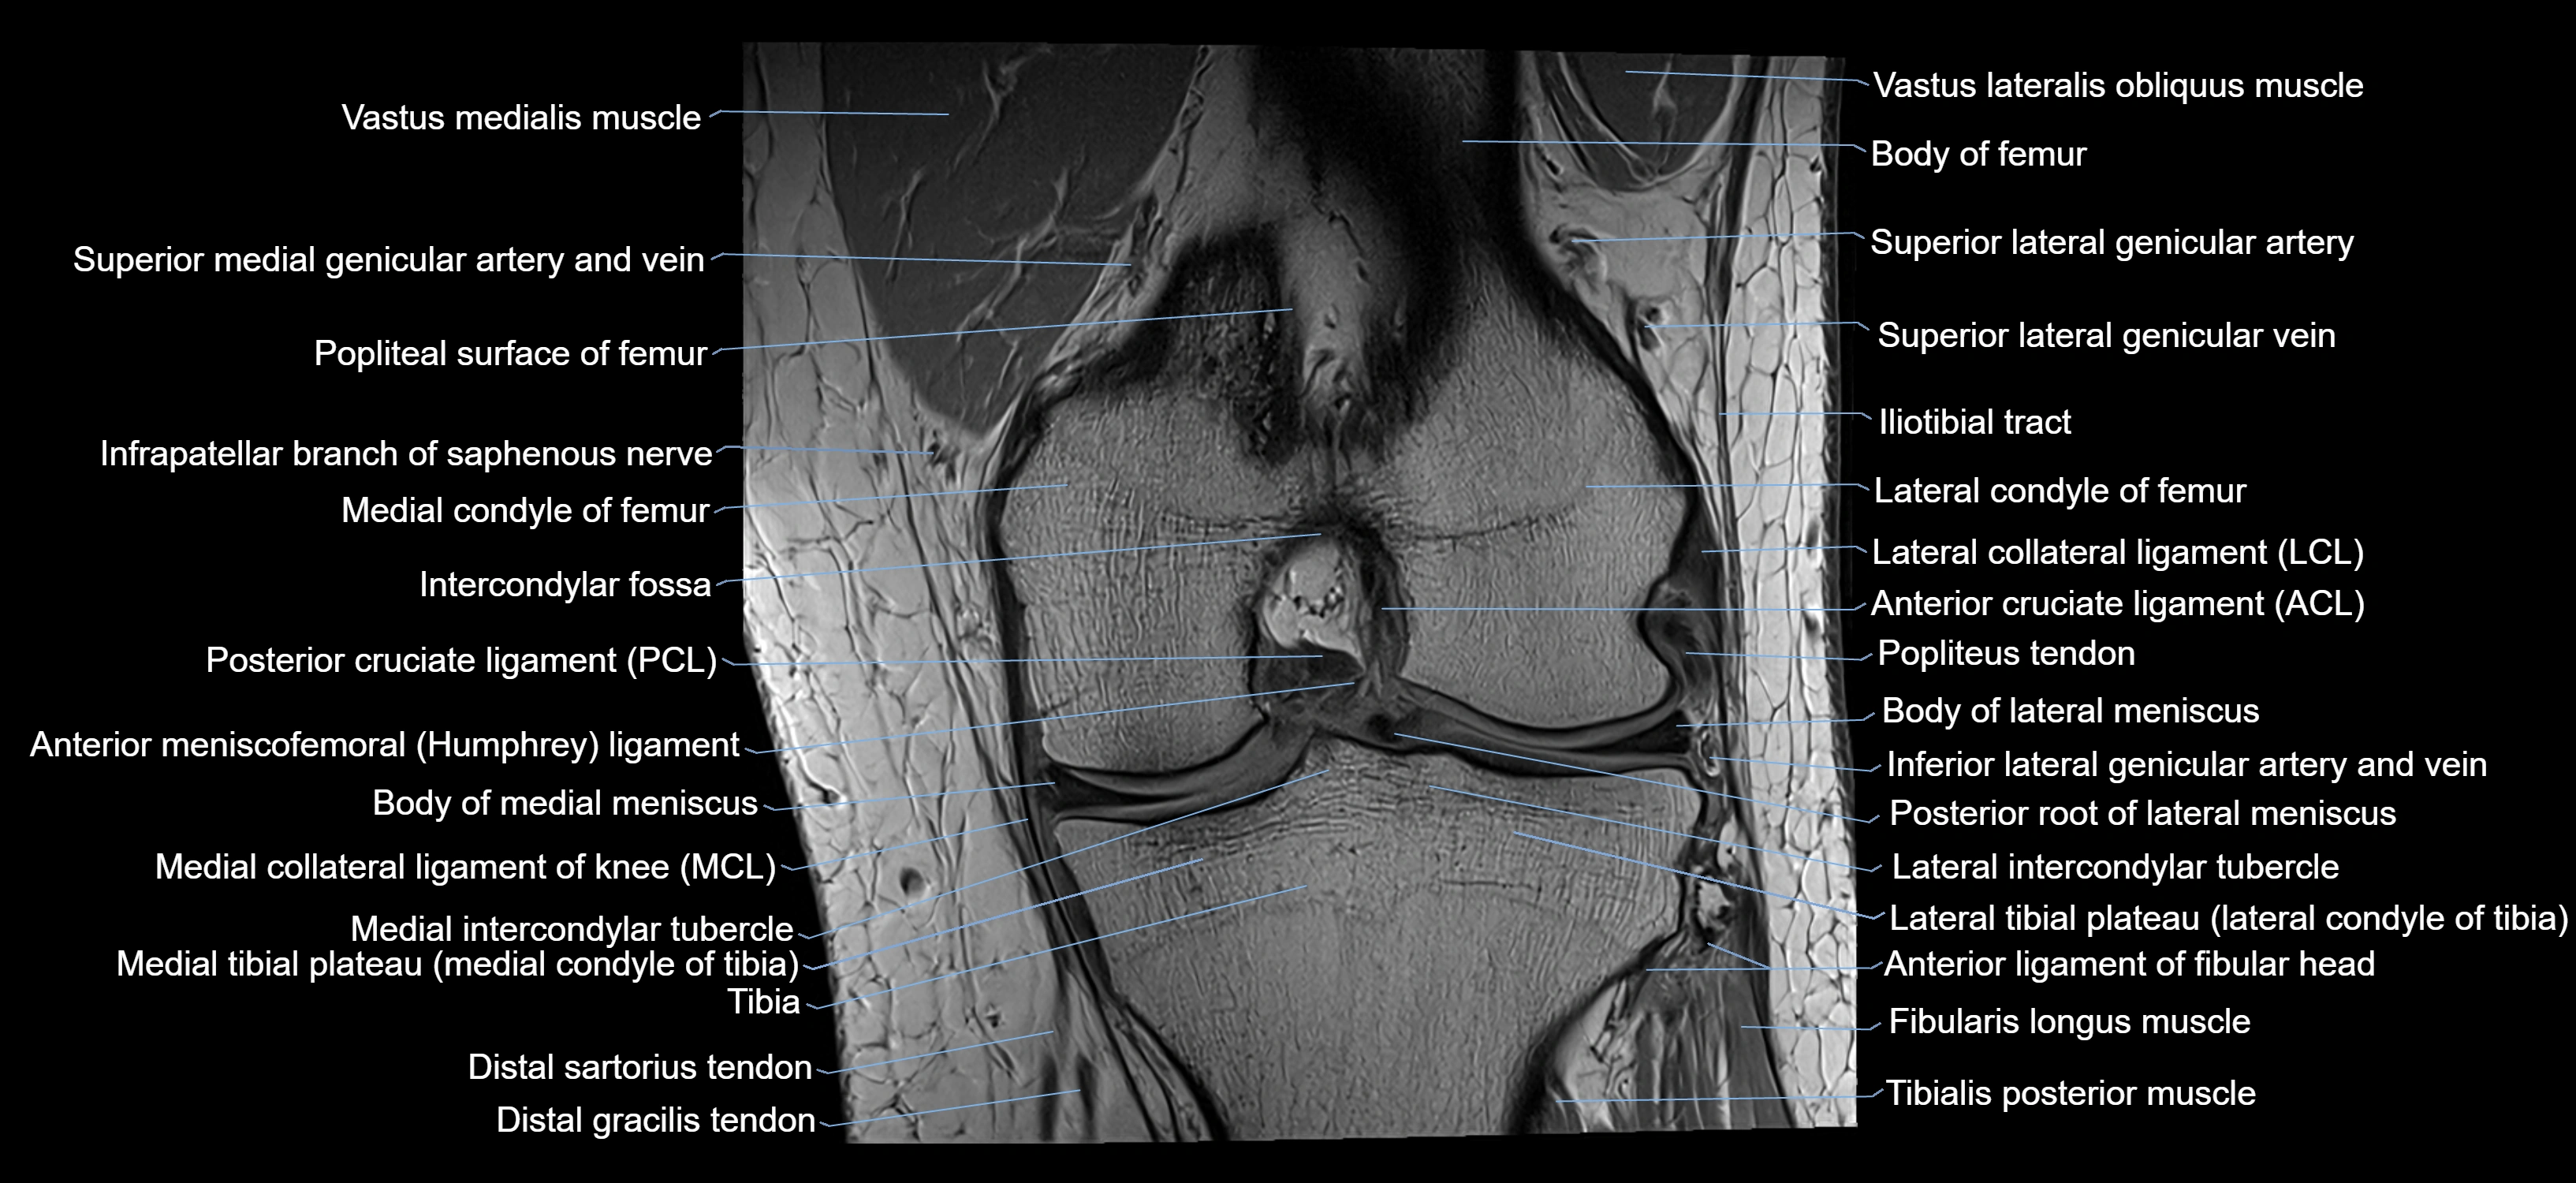

- Knee Joint

- Lateral collateral ligament

- Lateral condyle of femur

- Lateral condyle of tibia

- Medial collateral ligament

- Medial condyle of femur

- Medial condyle of tibia

- Medial intercondylar tubercle

- Medial meniscus

- Medial patellar retinaculum

- Posterior cruciate ligament

- Posterior horn of lateral meniscus

- Posterior horn of medial meniscus

- Posterior root of lateral meniscus

- Posterior root of medial meniscus

- Sartorius muscle

- Tibia